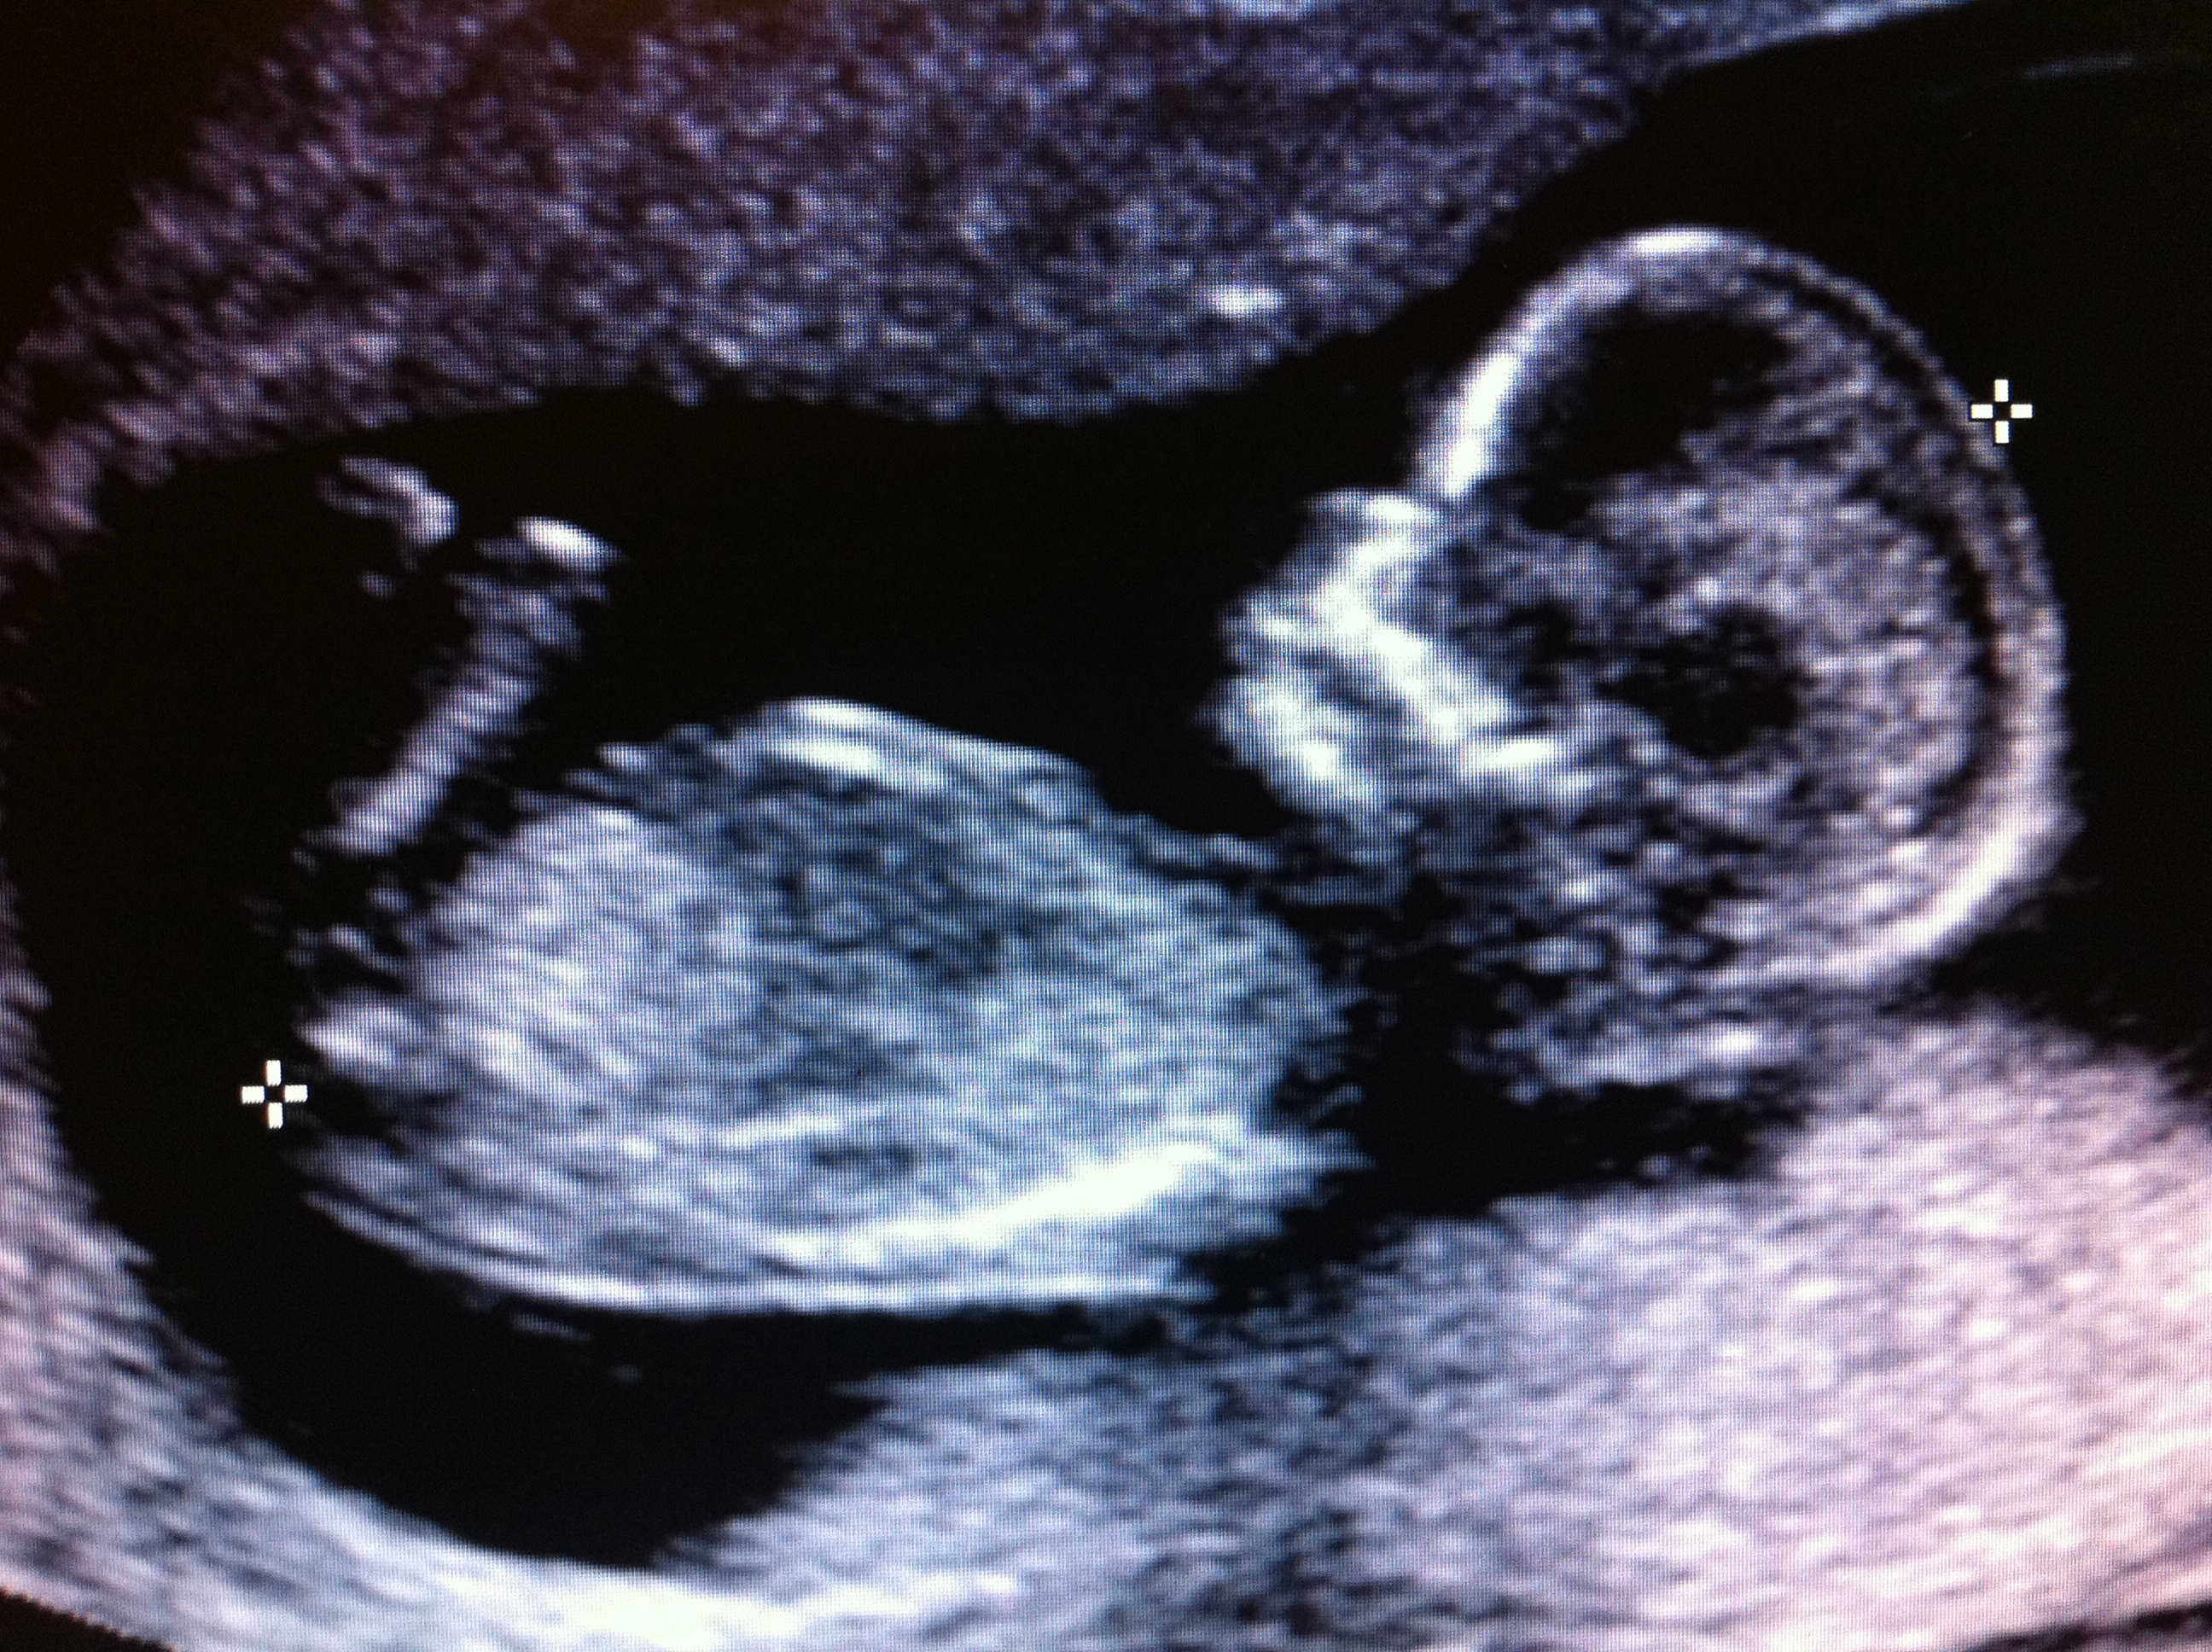

Skull or nub theory? Thanks

sorry I dont see a nub on this pic x

I guess boy

I would guess boy if that's the nub... It's short and stubby

No nub in this image.